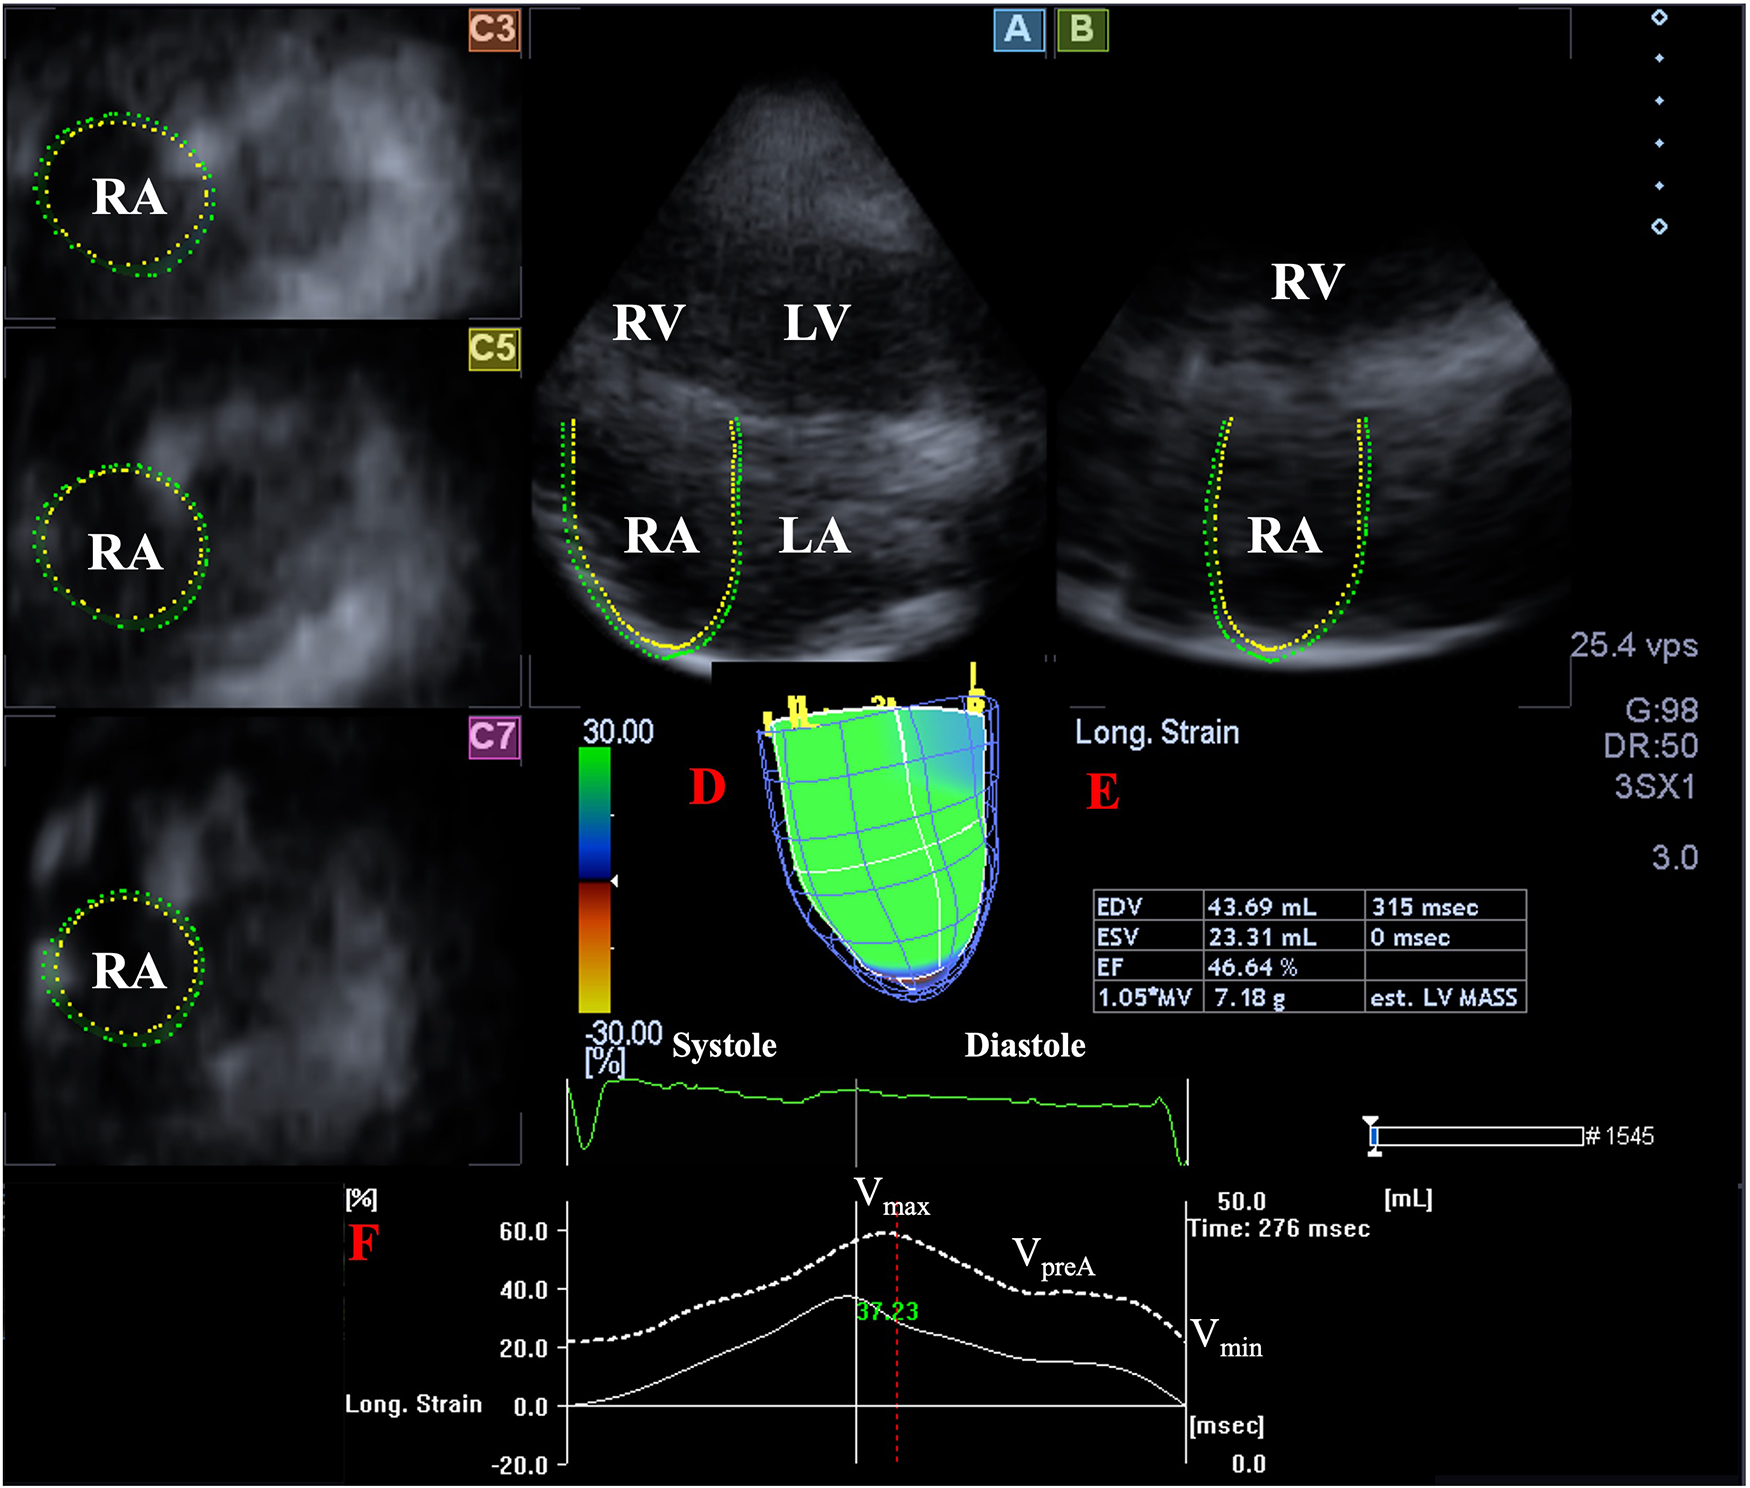

Later, offline analysis was performed with the vendor-provided 3D Wall Motion Tracking software version 2.7 (Ultra Extend, Toshiba Medical Systems, Tokyo, Japan). Data were displayed in selected apical two- (AP2CH) and four-chamber (AP4CH) views and 3 short-axis views at basal, midatrial and superior levels. To create a 3D cast of the RA, definition of reference points on RA endocardium were required in AP2CH and AP4CH views on the edges of the TA ring and the RA apex at end-diastole, then automatic sequential analysis (reconstruction) was performed for the complete endocardial RA surface. Taking into account the cardiac cycle, the following RA volumes were obtained (

Figure 1) (

14):

Maximum RA volume, measured at end-systole, just before tricuspid valve opening (Vmax).

RA volume before atrial contraction, measured at early-diastole at the time of the P wave on the ECG (VpreA).

Minimum RA volume measured at end-diastole, just before tricuspid valve closure (Vmin).

Figure 1

Three-dimensional (3D) speckle-tracking echocardiographic analysis of the right atrium in a healthy subject: apical longitudinal four-chamber (A) and two-chamber views (B) and 3 short-axis views at basal (C3), midatrial (C5) and superior (C7) RA levels. 3D virtual RA model (D), RA volumetric data (E) and time—global RA volume change curve (dashed white curve) and time—global RA longitudinal strain curve (white curve) respecting the cardiac cycle are demonstrated (F). LA, left atrium; LV, left ventricle; RA, right atrium; RV, right ventricle; EDV, end-diastolic volume; ESV, end-systolic volume; EF, ejection fraction; est., estimated; MV, myocardial volume; Vmax, maximum right atrial volume; VpreA, volume at the onset of atrial systole; Vmin, minimum right atrial volume.